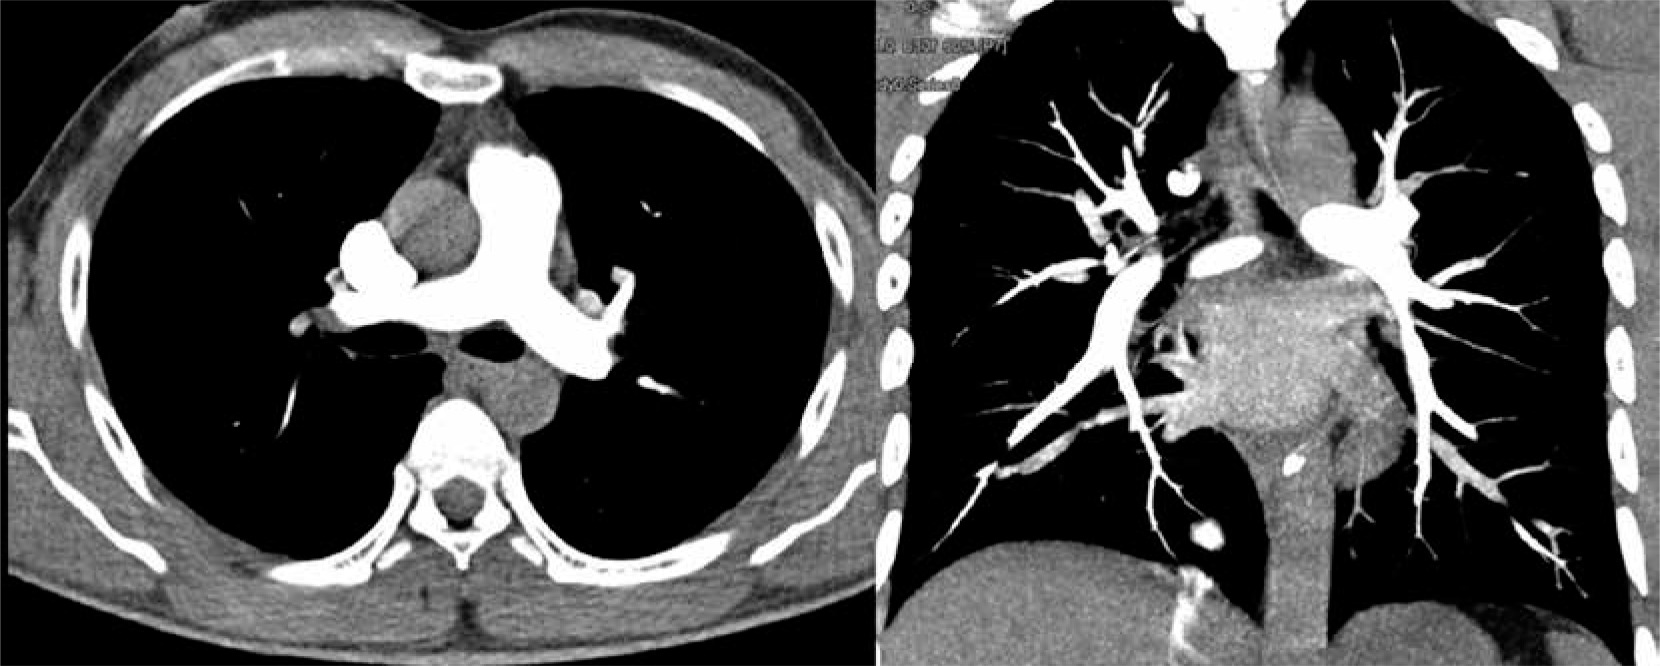

Figure 4

High-pitch PECG-gated CTPA in a 24-year-old male patient – axial and coronal images show uniform and dense opacification pulmonary arteries with quantitative enhancement in HU (MPA 396, right pulmonary artery 340, left pulmonary artery 354). Coronal image shows no intravascular shading (score 4) with visualization of subsegmental branches